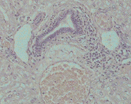

Liver - Fresh

Haematoxylin & Eosin (x100)

Rabbit Experiment